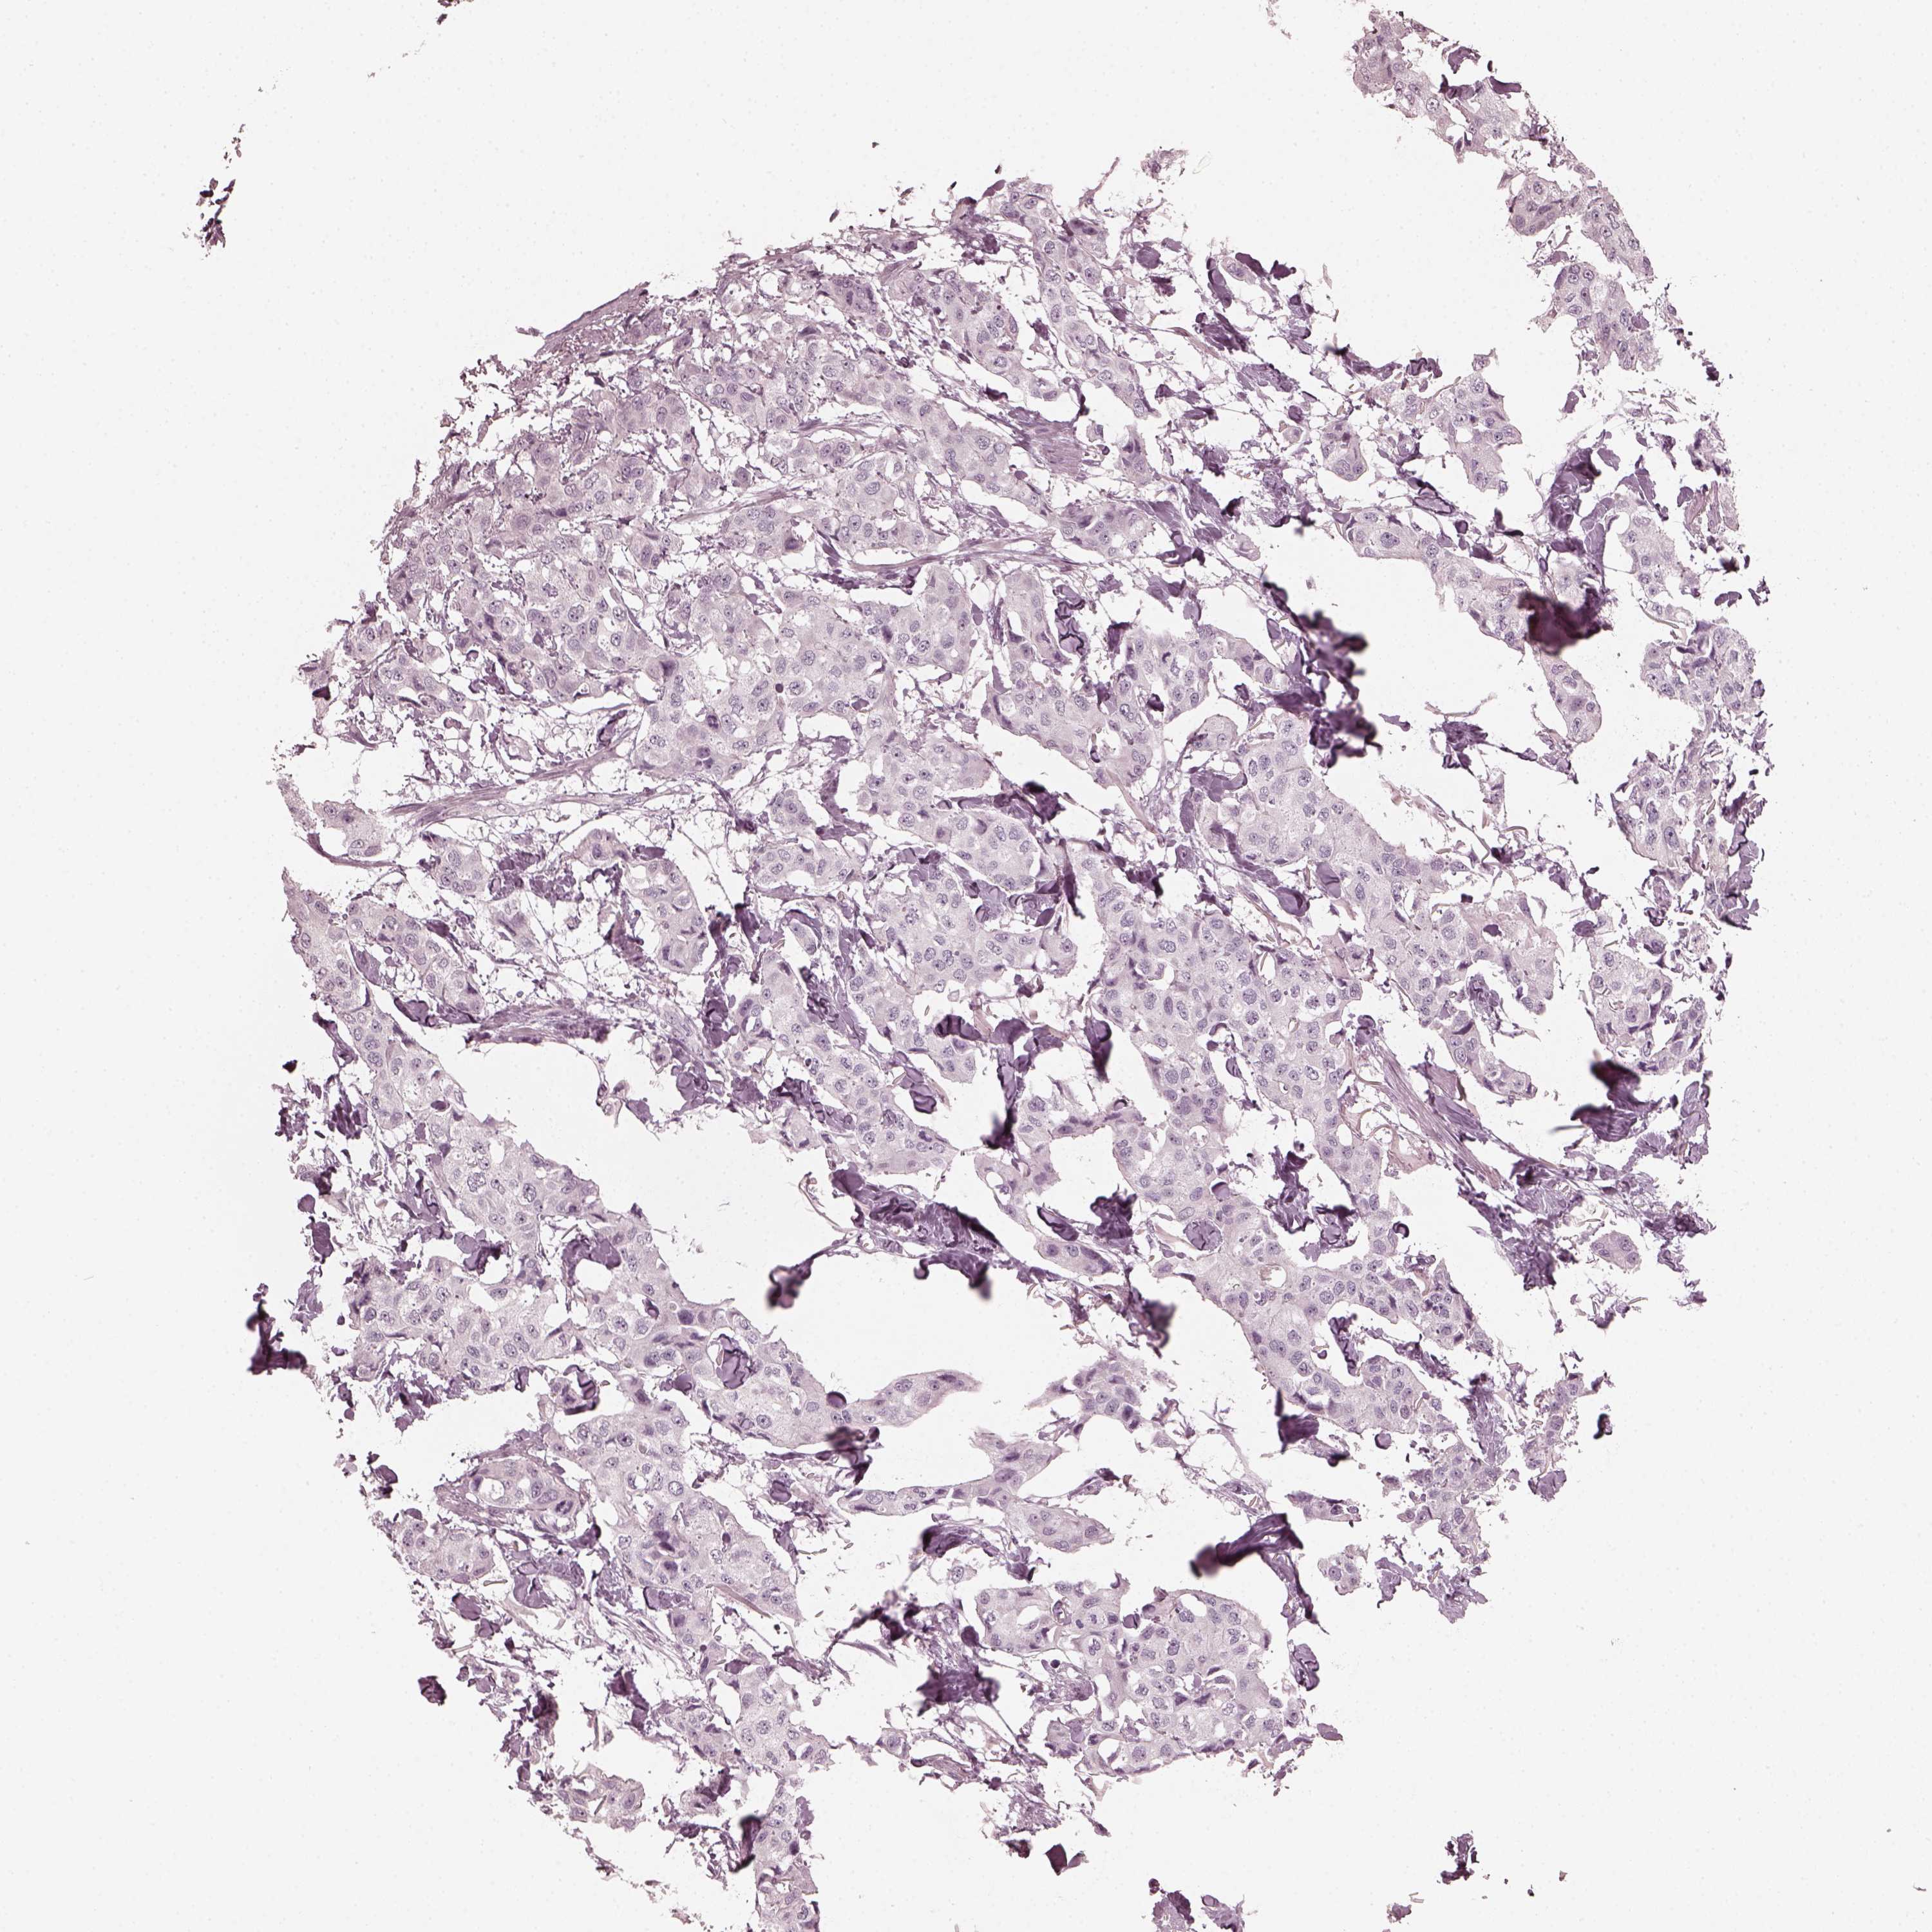

BRCA TCGA BRCA VALIDATION PROTEIN EXPRESSION